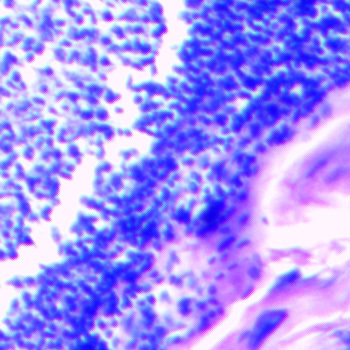

Pituitary BodyThe pituitary gland is an endocrine gland about the size of a pea. It is a protrusion off the base of the brain. The image of the pituitary body microscope prepared slide at left was captured at 400x magnification. You can learn more about the pituitary gland here |